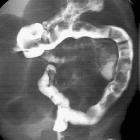

Fluoroscopy: contrast enema

Contrast enema may demonstrate a small caliber to the left colon with multiple filling defects within due to retained meconium. The rectum is usually normal in size, unlike Hirschsprung disease. The use of high osmolar ionic contrast media for enema in a neonate or infant is controversial due to the risks associated with fluid shift . The enema can be both diagnostic as well as therapeutic and is usually accompanied by the passage of meconium during or after the procedure.